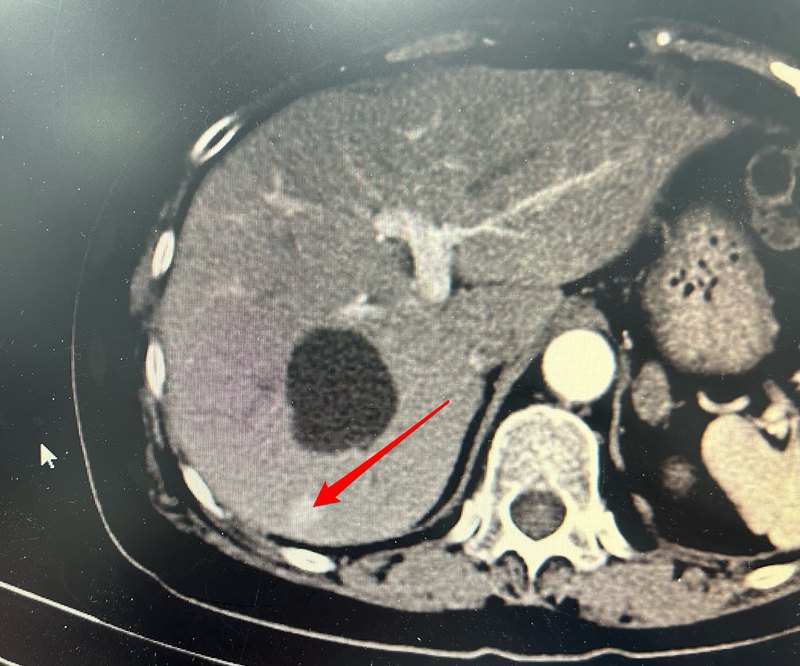

經(jīng)常有患者咨詢介入醫(yī)生是如何治療小肝癌的?下面分享一個小肝癌介入治療的過程供大家參考。右肝小肝癌,見紅色箭頭。其上方低密度灶為肝囊腫。先行介入造影及碘油栓塞減少腫瘤血供并標(biāo)志腫瘤位置。介入栓塞后病灶可見碘油沉積。CT引導(dǎo)下用微波消融針穿刺病灶并進(jìn)行消融治療。拔針后可見消融范圍呈低密度完全覆蓋腫瘤,提示腫瘤被完全消融。點評:小肝癌以往一般采取外科手術(shù)治療,隨著消融技術(shù)的不斷進(jìn)步,目前消融治療也是肝癌治療的首選方案,特別適用于難于耐受外科手術(shù)的患者。消融治療微創(chuàng)價格相對便宜,恢復(fù)快,未來會被更多患者選擇。